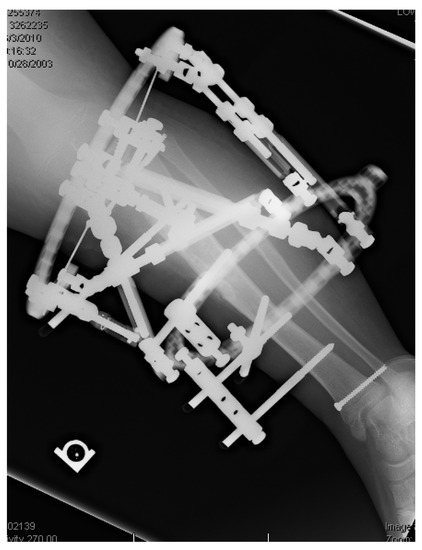

17. Gradual Correction with External Fixation